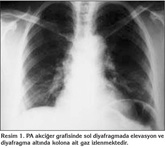

Elli sekiz ya??nda kad?n hasta, tekrarlayan ?ks?r?k ?ikayetiyle hastanemize ba?vurdu. Hasta ev han?m? idi ve sigara kullanm?yordu. ?yk?s?nde uzun s?redir nonprod?ktif ?ks?r?k ?ikayetine ek olarak s?k bo?az temizleme hissi ve bo?az a?r?s? mevcuttu. ?la? kullan?m ?yk?s? yoktu. Fizik muayenesi ve solunum fonksiyon testleri normal s?n?rlarda idi. Radyolojik tetkiklerinde; PA akci?er grafisi normal s?n?rlarda olan hastan?n waters grafisinde sa? maksiller sin?zit ile uyumlu bulgular? ve kontrastl? toraks bilgisayarl? tomografisi (BT)'nde diyafragma ?zerinde, sa? atriyum posterior kom?ulu?unda, ?VK'da anevrizmal geni?leme saptand? (Resim 1, 2). Yap?lan venografi incelemesiyle torasik ?VK segmentinde sakk?ler anevrizmal dilatasyon varl??? teyit edildi (Resim 3).